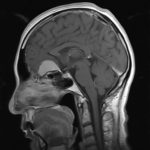

Cette masse peut entrainer notamment :

- Une irritation du cerveau qui se manifeste par une épilepsie

- Une compression voire destruction d’une partie du cerveau causant un affaiblissement ou une perte d’une fonction du cerveau

- Une augmentation de la pression à l’intérieur du crâne (espace inextensible à l’intérieur duquel vient s’ajouter le volume de la tumeur), ce qui va se manifester initialement par des maux de tête d’aggravation progressive qui vont s’associer à des nausées, des vomissements, des troubles visuels… Cet état peut aboutir à la perte de la vue dans les formes d’évolution lente et au décès dans les formes d’évolution rapide.